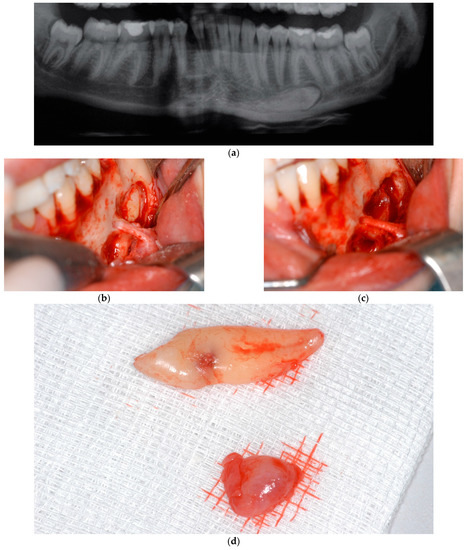

3. Results